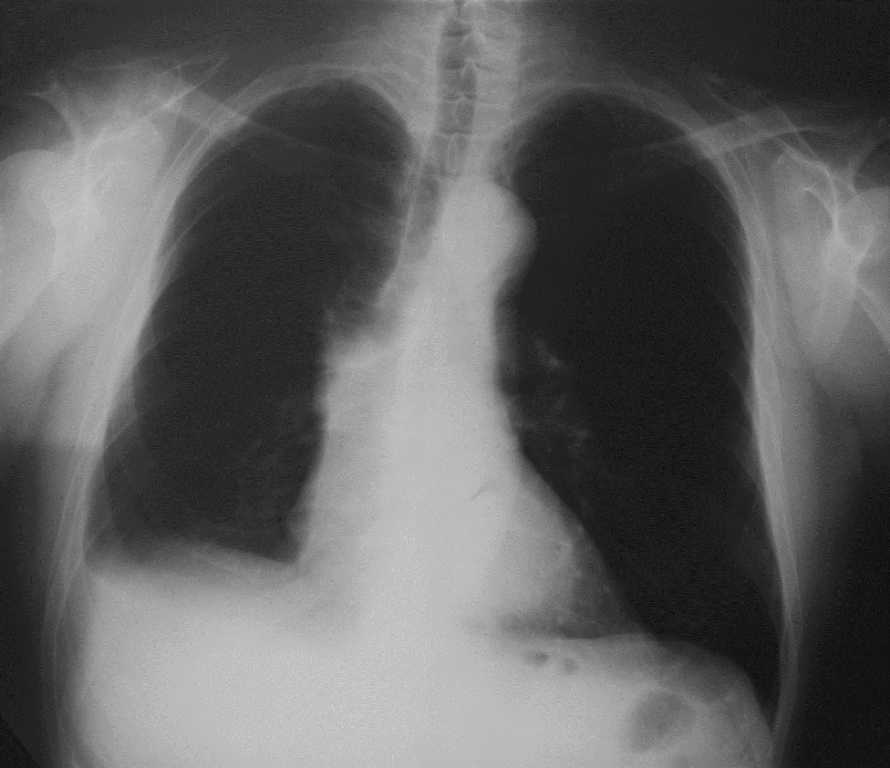

Keberhasilan GE tersebut tercatat dalam lembaran sejarah dunia. Tak cuma itu, GE juga pernah menyumbangkan kontribusi nyata dalam bidang kesehatan yang bermanfaat bagi kelangsungan hidup manusia, yakni inovasi X-Ray atau sinar-X. Penemuan sinar-X atau sinar Röntgen pada tahun 1895, menggerakkan periode dalam sejarah GE Healthcare di mana pencitraan tubuh manusia dikaitkan dengan merek inovasi. Penemuan Röntgen mencapai puncaknya pada 1970an. GE menjadi pemimpin peralatan sinar-X pertama yang melakukan gerakan kuat ke dalam pasar CT-ray computed tomography (CT).